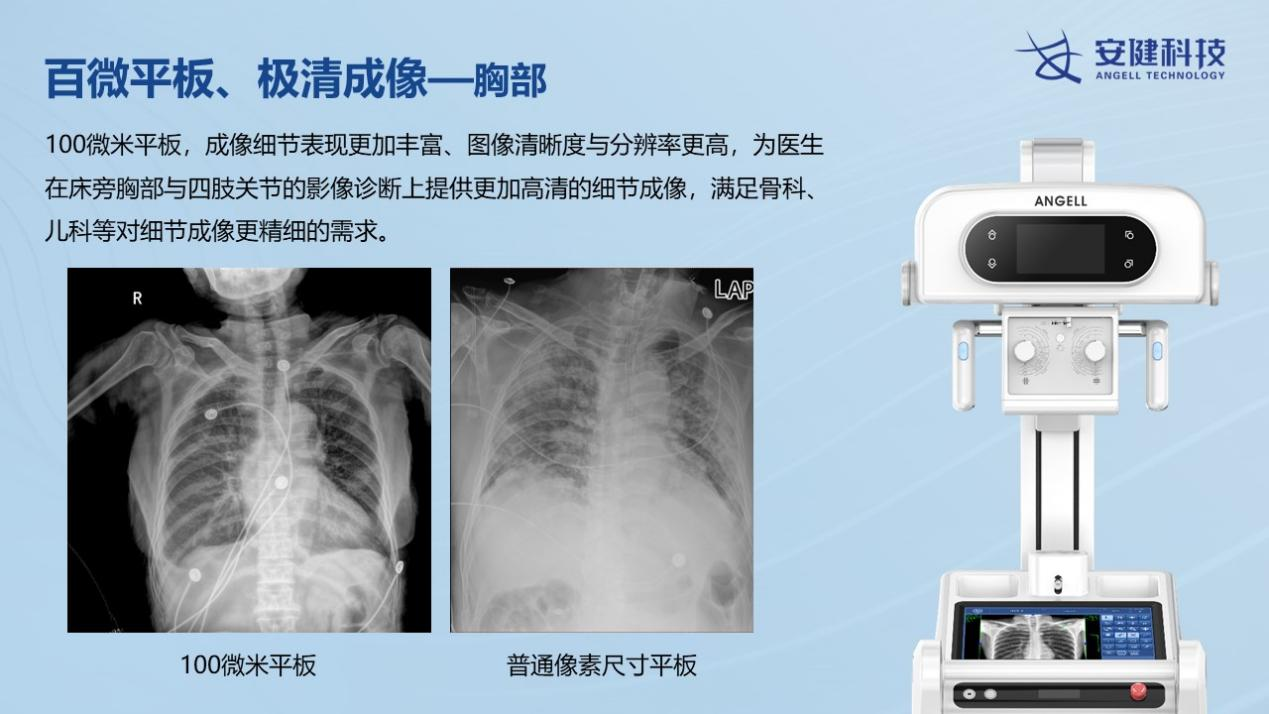

388vip太阳集团科技最新一代移动DR—飞燕Ⅱ,是国内首款大尺寸100微米超高清成像移动DR设备,具有1800万像素的超高分辨率,让床旁摄影的影像质量全面迈入高清时代。图像质量不仅远超当前市场上的移动DR设备,也远超过当前大部分固定DR设备的图像质量。

相较于普通DR的百万摄影像素,近2000万的高清像素,可以极大的提升床旁检查效率,包括骨科、新生儿科、心脏外科、重症监护科、急诊科等患者的快速检查。相较于目前市面上的低像素移动DR设备,100微米平板移动DR,在图像的分辨率、宽容度上都全面优于常规的130微米左右的移动DR设备。